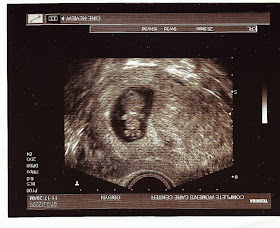

Week 8- Head is to the left, can kinda make out an arm and the feet

Week 8 - Head & chest (head to the left) On the ultrasound it looks like the baby is smiling, though the quality of the scanned image isn't as clear

Week 9 - Baby is facing forward, head on top. This one is my favorite b/c you can even see the sweet little face, and the arms and legs! It sure looks to me like there is something between the legs, but the dr. said "that" hasn't formed yet, so it is probably a tail or the umbilical cord.We are also starting to debate baby names! The girl is pretty much decided, although the middle name isn't set. We are still trying to decide a boy name, and have it narrowed down to two, but the middle name will for sure be Kyle (my maiden name). Help us decide by voting yay or ney on our choices: